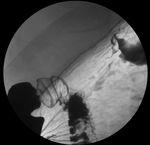

5. 4. 위암 검진

위 X선 검사 (바륨 검사)와 위 내시경 검사는 사망률 감소 효과가 증명되어 있으며, 대책형 검진과 임의형 검진 모두에서 권장된다.

펩시노겐법과 헬리코박터 파일로리 항체 검사는, 현 시점에서는 사망률 감소 효과의 증명이 불충분하지만, 충분한 설명을 거쳐 임의형 검진에 사용하는 것은 부정되지 않는다.[61]